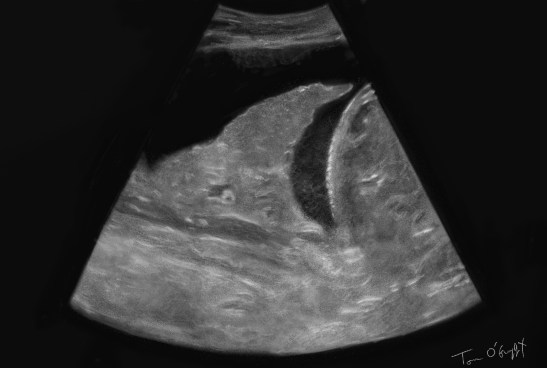

classification des aspects d’un épanchement pleural en échographie A anéchogène B complexe non cloisonné C complexe cloisonné D homogène échogène

Elle est très sensible pour le diagnostic d’épanchement pleural et le visualise nettement avant la radiographie thoracique (un peu sur le mode de la pneumopathie infectieuse). Elle visualise même la fluidité du liquide pleural quand il est totalement anéchogène. Elle permet donc immédiatement la distinction des différentes causes de poumon blanc radiologique (quand le déplacement médiastinal et trachéal n’est pas évident sur la RP). Il y a cependant toujours des corps flottants dans le liquide, en réglant le gain sur une image très claire, on peut clairement les voir, réalisant le signe du plancton.

Il n’y a pas forcément besoin de pratiquer l’échographie pulmonaire en tant que telle pour voir un épanchement, le positionnement de la sonde en RUQ et LUQ pour l’échographie FAST des polytraumatisés permet de les visualiser au-dessus du diaphragme. Dans cette vue, au bas de l’image on peut voir la ligne accidentée de la colonne vertébrale hyperéchogène, normalement non visible dans l’artefact aérique que constitue le poumon normal.

Le volume de l’épanchement peut être évalué sommairement en écho, d’abord « à l’oeil », puis par différentes méthodes, notamment en mesurant la distance entre le mur thoracique postérieur et la base du poumon. Pour cela il faut placer la sonde très postérieure regardant vers l’avant (PAPLS point), et plutôt se positionner en coupe transversale. On choisit la distance la plus éloignée entre la paroi et le poumon et on multiplie le chiffre obtenu en mm par 20 pour obtenir un volume approximatif en ml.

L’épanchement n’est pas toujours fluide et comporte parfois des septas créant ainsi différentes poches et collections.

épanchement cloisonné avec septas entre la base des poumons et le diaphragme. Consolidation pulmonaire avec artefact en queue de comète (pas une ligne B car ne venant pas de la ligne pleurale)

Enfin, mais ce n’est pas le propos en urgence, l’effusion réalisant une fenêtre acoustique intéressante, le poumon sous-jacent et le diaphragme peuvent être analysés (consolidation d’une pneumonie, atélectasie, masse pleurale).

En échographie cardiaque, on peut parfois confondre un épanchement péricardique et un épanchement pleural, la différence se notant par rapport à la position de ce croissant anéchogène vis à vis de l’aorte thoracique (plus postérieur pour l’épanchement pleural).